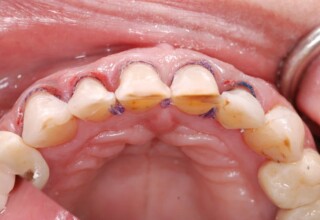

Ολική Στοματική Αποκατάσταση σε Εμφυτεύματα με διαφορετική προσέγγιση στην Άνω και Κάτω Γνάθο

Κάτω γνάθος: εξαγωγές, άμεση τοποθέτηση εμφυτευμάτων και άμεση φόρτιση(την ίδια ημέρα) με προσωρινή γέφυρα

Άνω γνάθος: σταδιακές εξαγωγές, σταδιακή τοποθέτηση εμφυτευμάτων και σταδιακή ενσωμάτωση τους στην προσωρινή γέφυρα ώστε η ασθενής να μην μείνει ούτε μια ημέρα χωρίς αποκατάσταση. Στόχος η συνεχής λειτουργική και αισθητική αποκατάσταση της ασθενούς χωρίς άμεση φόρτιση των εμφυτευμάτων λόγω ανατομικών ιδιαιτεροτήτων.

Χρησιμοποιήθηκαν παλαιές χαμογελαστές φωτογραφίες της ασθενούς γιατί είχε χαθεί τελείως το φυσικό σχήμα των δοντιών εξαιτίας των πολλαπλών προσθετικών προσπαθειών που είχαν γίνει στο παρελθόν. Μεταφέρθηκε στην προσωρινή γέφυρα η σχέση των φυσικών δοντιών μεταξύ τους άλλα και με τα χείλη. Δοκιμάστηκε η φώνηση και η μάσηση με δυο διαφορετικές προσωρινές άνω γέφυρες και εκτιμήθηκε η αισθητική απόδοση τους. Αφού επιτεύχθηκαν σε βαθμό ικανοποιητικό η φώνηση και η αισθητική εμφάνιση της οδοντοφυΐας, η προσωρινή αποκατάσταση χρησιμοποιήθηκε ως οδηγός για την τελική.

Αρχικό

Ενδιάμεσο

Τελικό